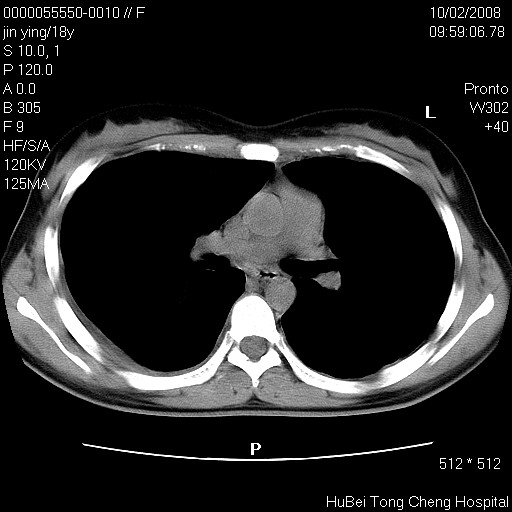

患者 女,18y。发热十余天,伴咳嗽。pe:t39⒈℃,bp 110/80mmhg,p 86次/min。神清,精神欠佳。双肺可闻及少许湿罗音。既往史不详。

临床诊断:肺部感染?

胸部ct轴位平扫(层厚10mm,螺距1.5,重建间隔10mm),图像如下: